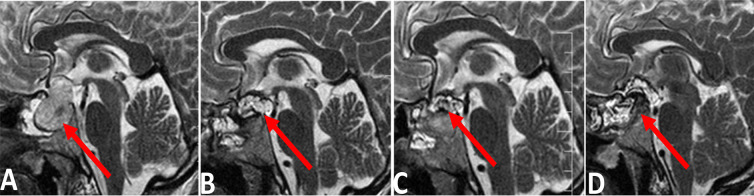

Methods: A total of 28 patients with pituitary adenoma were evaluated. All patients did four sellar MRIs. The first MRI was done before surgery, and three were done 48 hours, two weeks, and three months after the surgery. Finally, the MRI findings at different times were compared to each other.

Results: The pituitary gland and adenoma signals were constant at all time points. The signal of the packing material showed no differences in T1-weighted and T1-weighted with contrast sequences but showed changes in T2-weighted sequences.